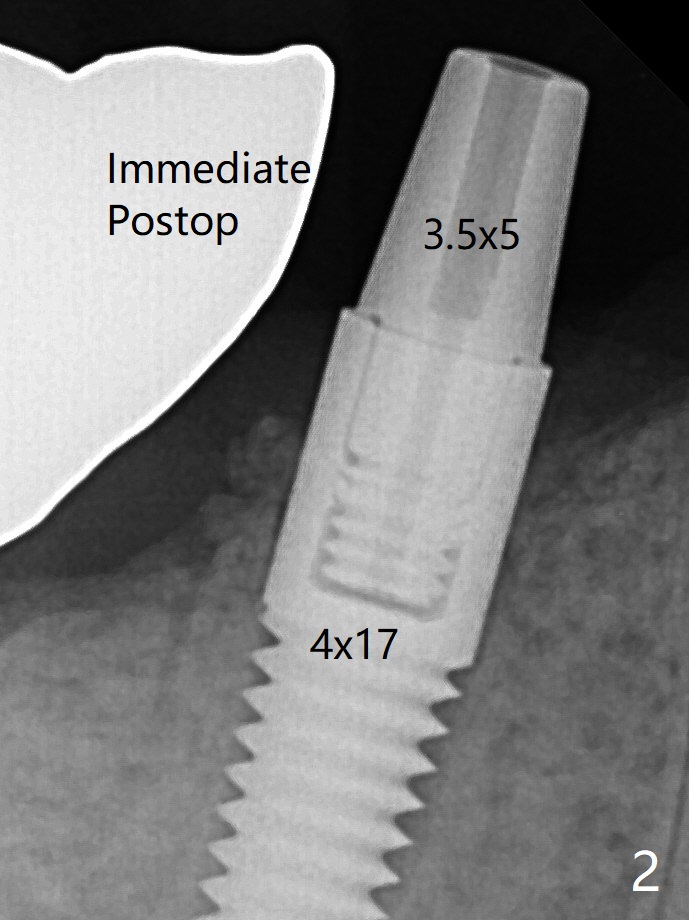

植体长度     Last     Next